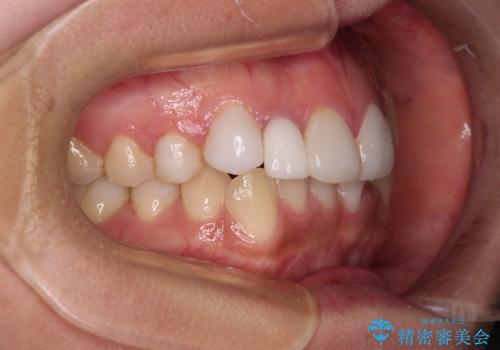

前歯のデコボコが気になる インビザラインによる矯正治療

- 上下前歯のデコボコを気にして来院された患者様です。

インビザラインによる上下歯列の拡大と、IPR(歯と歯の間を削る)にるスペースの獲得により、前歯のデコボコを改善することとしました。